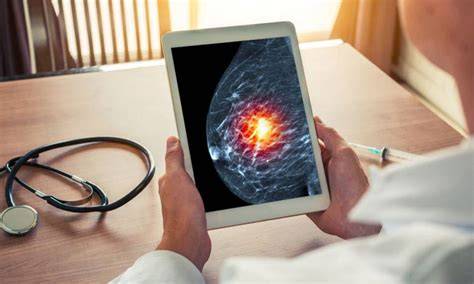

L’intelligence artificielle s’impose comme un appui crédible dans le dépistage du cancer du sein. Selon une vaste étude publiée dans The Lancet, son utilisation dans la lecture des mammographies permettrait de détecter davantage de cancers, tout en allégeant le travail des radiologues.

Menée en Suède sur près de 106 000 mammographies réalisées entre 2021 et 2022, l’étude a comparé deux méthodes. D’un côté, une double lecture humaine classique. De l’autre, une lecture assurée par un radiologue assisté par une intelligence artificielle. Les participantes avaient un âge médian de 53 ans.

Résultat majeur : le dépistage assisté par l’IA a permis d’identifier 81 % des cancers, contre 74 % sans recours à l’outil numérique, sans hausse des faux positifs. Autre point notable, les femmes suivies avec l’aide de l’IA ont présenté, dans les deux années suivantes, moins de cancers agressifs ou à un stade avancé, avec une baisse estimée à 12 %.